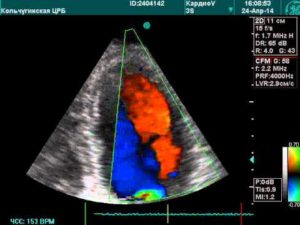

Наиболее точный метод обнаружения фистулы между аортой и легочной артерией – УЗИ сердца с допплерографией.

Отверстие или проток могут быть расположены на любом участке в месте соприкосновения магистральных сосудов, их диаметр варьирует от 1 — 2 мм до 2 — 3 см.